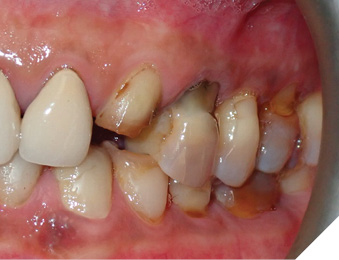

A 65-year-old woman comes to the office with the chief complaint of worn-down teeth, missing teeth, tooth sensitivity, especially on maxillary teeth and TMJ pain. Her past medical history was reviewed and was significant for asthma, insomnia, hypercholesterolemia, hypothyroidism, and anxiety disorder. She denied any sleep disturbances. Her medications included salbutamol, ezetimibe, quetiapine, and levothyroxine. She referred to being allergic to dust and shellfish and sensitive to propofol. She had a right mastectomy in 2014 due to breast cancer. No chemotherapy or radiation was done. Her diet was considered normal, and she denied any consumption of acidic drinks and denied any history of regurgitation. She denied any parafunctional habits during the day. She was using a maxillary transitional partial denture since she had lost some of her teeth due to fracture and caries. No other problems were evidenced. Intraoral exam showed moderate attrition lesions of posterior teeth, porcelain fused to metal crowns on teeth 46 and 47 had the porcelain portion worn down, exposing the metal substructure. Missing teeth included teeth 14,15,16,18,24,28, 36,38,48. Palatal surfaces of maxillary anterior teeth also appeared worn down. An abfraction lesion was found on tooth 23. No carious lesions were found in any of her teeth. Composite restorations on mandibular anterior teeth were chipped or were missing (Figs. 6-11) She also presented with limited mouth opening: 35 mm interincisal distance at maximum opening. There was bilateral pain on palpation of preauricular areas. Her pain was the worst early in the morning which suggested night parafunction. No crepitus, or joint clicking were found.

Fig. 8

Articulated diagnostic casts showed very limited to no overjet and 90% of overbite. The wear pattern on the palatal aspect of her maxillary teeth appeared to be secondary to her tight occlusion since mandibular anterior teeth were in close contact with these surfaces with no “room” for protrusive movements. The diagnosis for this patient was: partial edentulism, failing existing restorations and attrition and abfraction secondary to parafunction. We discussed different options, including orthodontics in order to increase her overjet so we could have prosthetic space to restore her worn down teeth. We also discussed tooth replacement options. After a second consultation appointment which she attended with her husband, she decided that she did not want to replace her teeth with removable prosthetics. She also declined referral to an orthodontist. After discussion of multiple options of treatment to address all her chief complaints, her treatment consisted of a full mouth reconstruction with full coverage restorations in Zirconia for teeth 11-13,17,22-23,25-27,32-42, 44-47 and partial coverage restorations with lithium disilicate restoration for teeth 33,34 and 43. Replacement of teeth was achieved with a fixed partial denture to replace tooth 36 and a 3-unit implant supported bridge to replace teeth 24-26. In terms of occlusion, we created a more favorable occlusion with a proper anterior guidance, canine disclusion with more freedom for protrusive movements, which hopefully would decrease the parafunction, and alleviate some of her muscle pain. Before completing the case, the patient spent several weeks with provisional restorations which reflected the increase in vertical dimension of occlusion and the new occlusal scheme. During this trial phase, we assessed comfort, esthetics, function, decrease in pain and speech (Figs. 12-17).